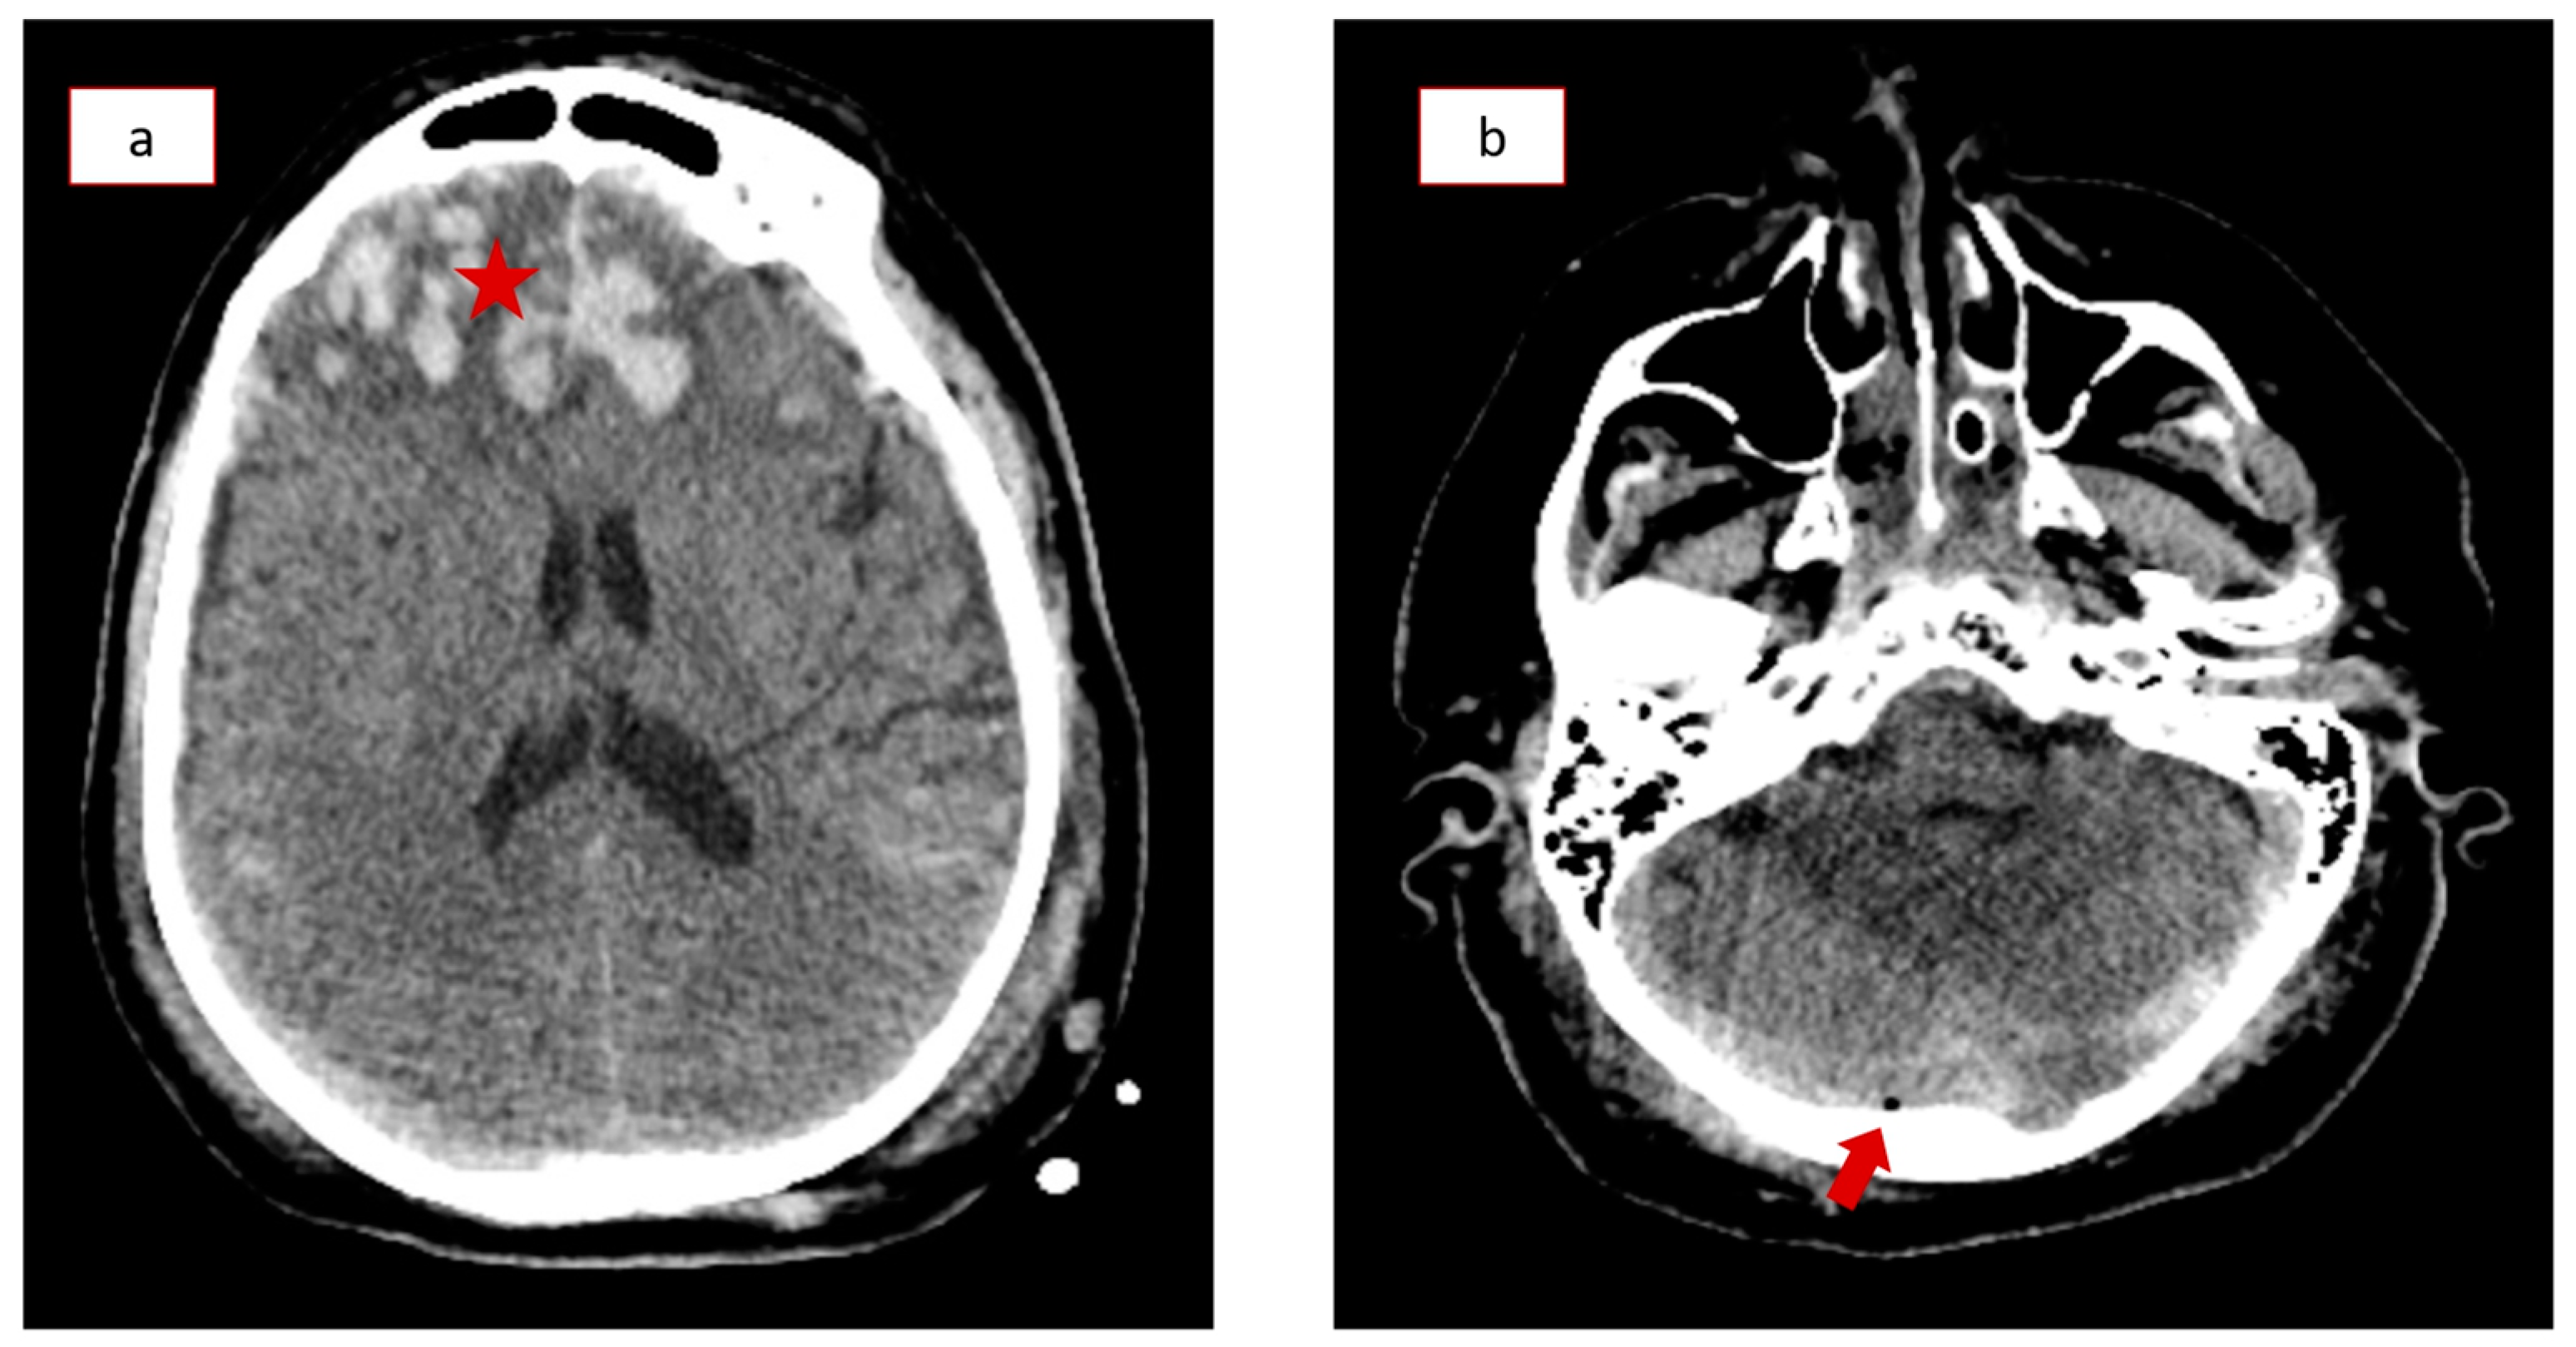

This study’s case presentation concerns a 66-year-old male patient with an unremarkable past medical history who suffered a moderate traumatic brain injury (TBI) following a 4 m fall. He was immediately transferred to the nearest regional emergency department with an initial Glasgow Coma Scale of 10 out of 15 and mild hemodynamic instability. The patient was intubated, and after primary stabilization, he underwent a full-body computed tomography (CT) scan. Brain and cervical spine CT scans showed several cerebral contusions, pneumocephalus, subdural hematomas, subarachnoid hemorrhage, a fracture of the petrous portion of the temporal bone (Figure 1a,b), and an undisplaced fracture of the second cervical vertebra (Category III of Marshall tomographic score; Injury severity score score of 16). The patient was then transferred to a tertiary hospital intensive care unit with neurosurgical support due to the severity of his condition. Initial ICP measurements (Natus Camino intracranial pressure monitoring catheter, Middleton, WI, USA) were less than 6 mmHg. However, he soon developed several episodes of intracranial hypertension, with ICP measurements as high as 30–35 mmHg, and an external ventricular drain had to be inserted to resolve the condition.

Figure 1.

Computed Tomography (CT) scanning upon admission of the patient. (a) Hyperdense lesions representing subarachnoid hemorrhage and bilateral cerebral contusions (asterisk). (b) Small intracranial collection of air below the occipital bone (arrow).